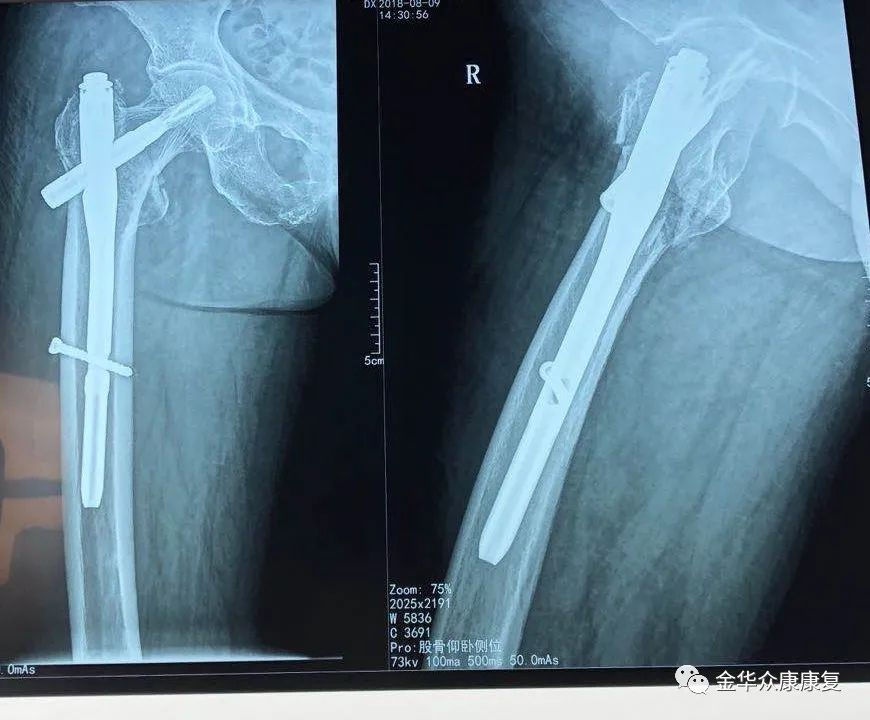

骨科:专业开展急诊创伤、骨关节疾病的治疗,手术及微创治疗四肢、关节骨折、髋膝关节置换、颈腰椎疾病。中医正骨、介入治疗、闭合穿针内固定、经皮撬拔复位、小针刀、水针刀、神经根阻滞、骶管注射、封闭、骨牵引等多种治疗手段。